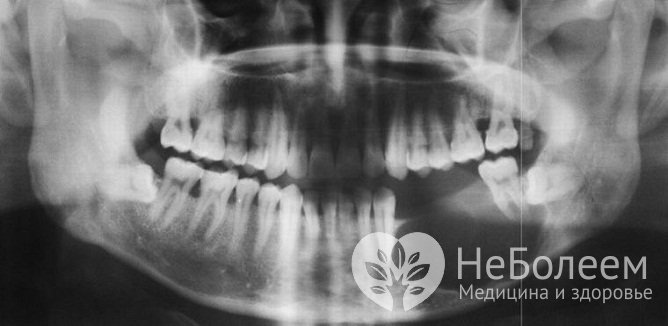

Амелобластома на рентгеновском снимкеАмелобластома требует дифференциальной диагностики с плоскоклеточным раком челюстно-лицевой области, цистаденоидной карциномой слюнной железы, дентальными кистами, вызванными воспалительным процессом.